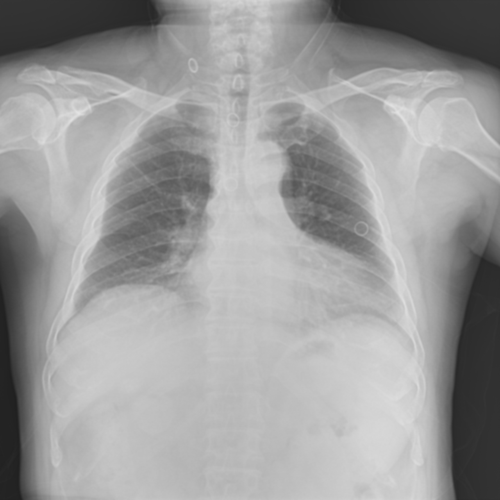

To pre-train a high-performance X-ray foundation model, the first thing we need to do is the collection of large-scale X-ray images. Therefore, a large-scale and high-resolution dataset that contains X-ray medical images is collected for the pre-training. Some representative samples are visualized in Fig. 3.